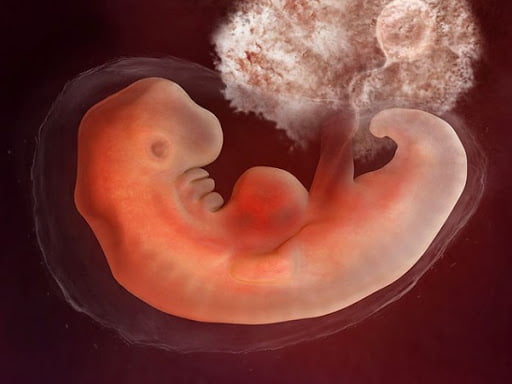

در هفته ششم بارداری، کودک شما تقریباً 1.8 – 1.4 اینچ طول دارد. تقریباً به اندازۀ یک دانه انار. او شبیه به یک بچه قورباغه به نظر می رسد. با یک دم کوچک که به ستون فقرات تبدیل خواهد شد. جوانه های ریزی در راه تبدیل شدن به دست، پا و گوش هستند. مغز، ریه ها و سایر اندام ها نیز در حال رشد هستند. اجزای صورت نیز در همین هفته شروع به شکل گیری می‌کند. دندان ها و یک لایه نازک از پوست وجود دارد. ضربان قلب کودک اغلب با سونوگرافی واژن در این مرحله از بارداری قابل تشخیص است.

در جایی که قلب تشکیل شده است، یک برآمدگی و در جایی که سر قرار دارد، یک حالت تحدب دیده می‌شود. دست و پاهای ریز شروع به شکل گیری می کنند و به عنوان جوانه اندام شناخته می شوند. رویان با لایه نازکی از پوست شفاف، پوشانده شده است. به طور کلی، در این زمان جنین شما هنوز شبیه به یک کودک نیست.